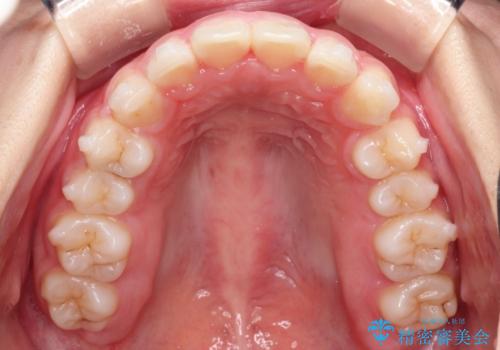

- 前歯の隙間と、出っ歯に見えることを主訴に来院されました。

できるだけ目立たない装置をご希望されましたので、インビザラインにて治療を行いました。

治療中は、できるだけ前歯を下げることができるように”顎間ゴム”を使用します。